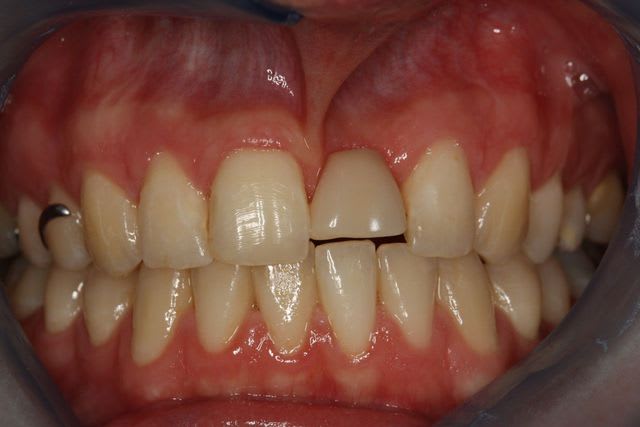

avant tout très beau cas avec une indication bien posée et une belle réalisation.

Par contre une petite remarque pourquoi avoir fait une couronne aussi triangulaire? Accentuer le coté rectangulaire aurait permis une formation et un maintien plus facile de la papille distale. De plus cela aurait plus symétrique. Donc plus esthétique.

En dehors de ça je le répète c'est un très beau cas, la remarque que je fais est je l'éspère constructive.

pour la forme de la couronne c'est vrai, je suis 100% d'accord.

Mais comme le patient ne découvre pas, c'est pas trop important pour lui.

on ne s'attend pas à ce résultat au départ, la papille est la, malgré les "reproches" sur la forme de la couronne.

ndecer: "Par contre une petite remarque pourquoi avoir fait une couronne aussi triangulaire? "

parce que le patient n'avait pas les €€€ pour que notre chicot prépare le profil d'émergence gingival par une provisoire implantoportée. Mais ça mon chicot tu vas nous le faire la prochaine fois hein!( et même si le patient n'a pas les sous, just for fun and very beautiful result)

Malgré la 'finition au labo' le glaçage est trop marqué, ce qui rend la dent un peu trop brillante par rapport au autre d'ou l'aspect chouilla trop neuf. mais a part nous avec nos yeux trop exigent qui le voit ?